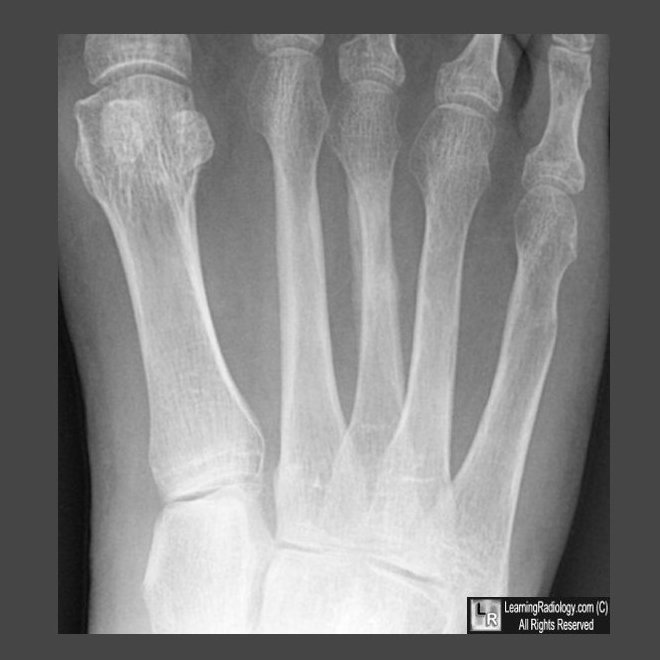

Fracture surface

Fracture surface 114 фото